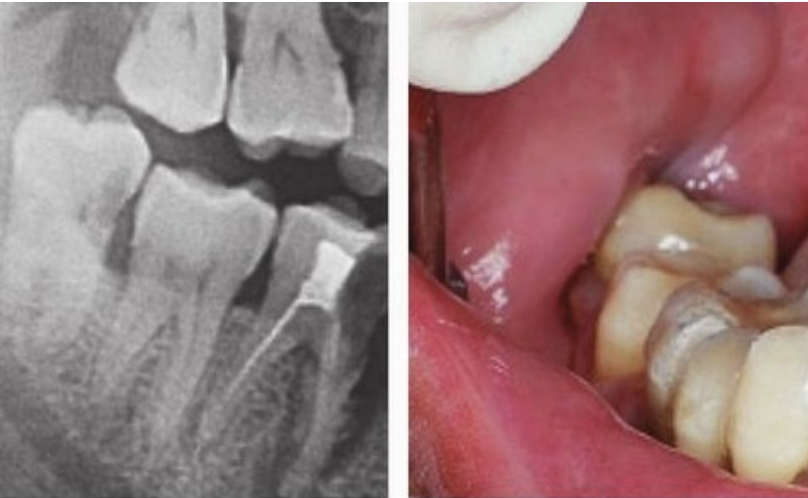

拔牙前拍 X光片可以讓醫(yī)生看到肉眼看不到的牙根形態(tài)、生長(zhǎng)狀態(tài)。

根據(jù) X光片的結(jié)果,醫(yī)生可以更地評(píng)估拔牙的難度,定制拔牙的方案,向患者更好地解釋一些可能存在的風(fēng)險(xiǎn)。

此外,有時(shí)候X光片還能發(fā)現(xiàn)肉眼看不見的斷在牙槽骨里的殘根,在手術(shù)時(shí)可以對(duì)拔除殘根更加地有把握。

(術(shù)前進(jìn)行拍片,確定牙齒情況)